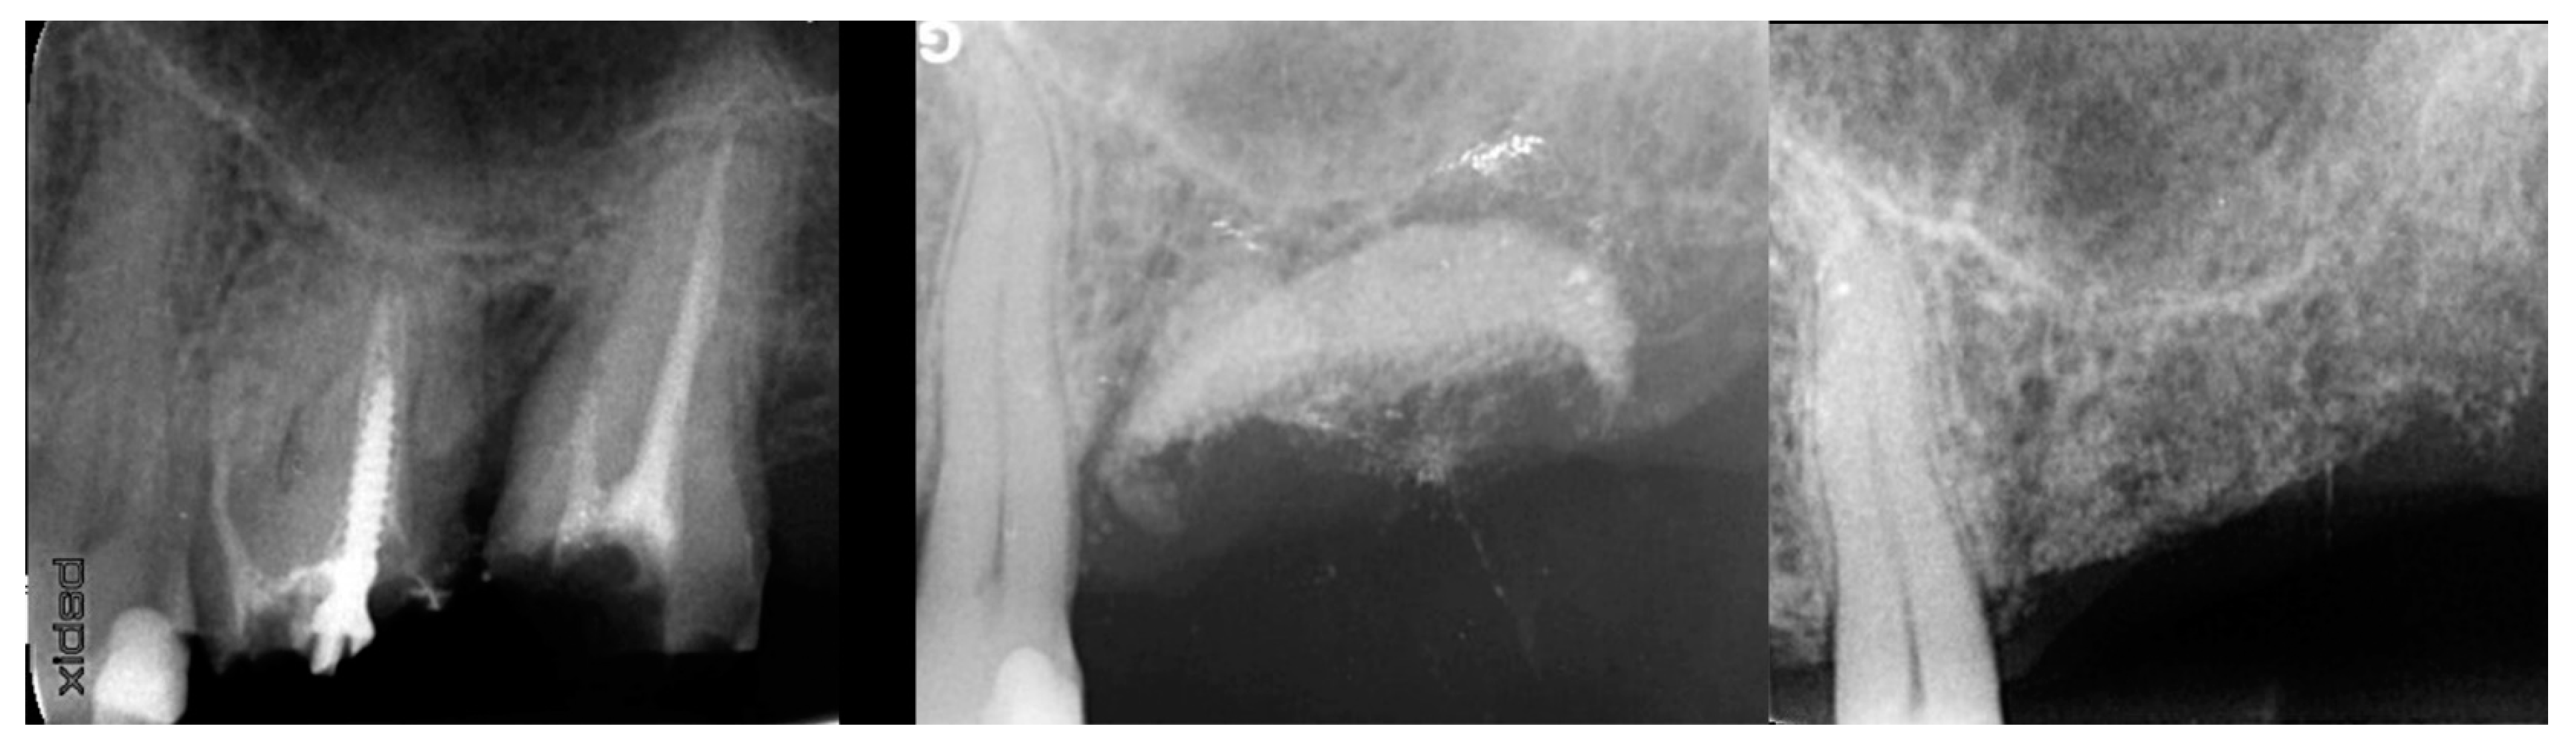

Figure 8.

Failing 1st and 2nd molars related to periodontal bone loss (left), the site following 10 weeks of healing to allow soft tissue closure over the ridge (middle) and a radiograph demonstrating the available bone between the crest and sinus for implant placement (right).

At 10 weeks post-extraction, the patient presented, and consent forms were reviewed and signed for grafting and implant treatment. Soft tissue had healed, closing the site with keratinized tissue (Figure 8, middle). A radiograph was obtained to check what available bone was present at both sites (Figure 8, right). Sufficient height was available to place an implant at the 1st molar site in conjunction with a crestal sinus augmentation, but insufficient height was present at the 2nd molar site which would require grafting to increase crestal height and later implant placement could be performed at that site.

Figure 9.

Site was reentered at 10 weeks post-extraction and an implant was placed with a crestal sinus augmentation utilizing EthOss graft material at the 1st molar site and a large defect was present at the 2nd molar site (left), with a radiograph obtained to document the implant placement at the 1st molar and grafting of the defect (middle) and following crestal grafting of the 2nd molar site (right). Green line is the measurement of the height of the bone at that point between the crest and the sinus floor.